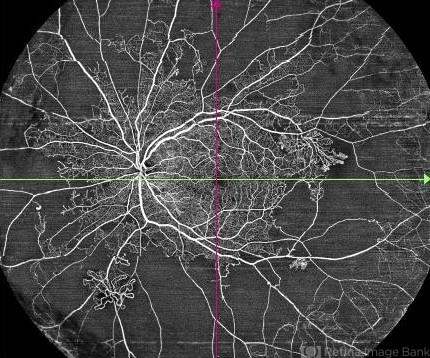

- proliferative diabetic retinopathy (PDR), ultra-wide field imaging, OCTA

Widefield Optic Coherence Tomography Angiography (WF-OCTA). - Description

- This is widefield optic coherence tomography angiography (WF-OCTA) picture of LE of a diabetic patient. This patient had Proliferative Diabetic Retinopathy and depicts large areas of capillary non perfusion with neovascularization elsewhere.